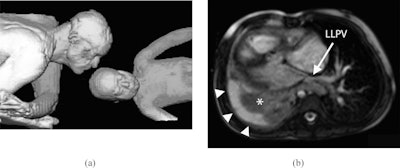

(A) Volume-rendering reconstruction of father and daughter in MRI scanner bore. (B) Axial image from a steady-state free precession acquisition. LLPV = left lower pulmonary vein.In one case highlighted in the series, the authors used the technique in a 2.5-year-old girl born with several heart defects. The girl had undergone biventricular repair and developed right lower and middle pulmonary vein stenosis and presented with recurrent pneumonia and chronic right pleural effusion.

The girl underwent cardiac MRI together with her father. All images were acquired during free breathing, and pauses in scanning were minimized to shorten scan time and allow the patient to focus her attention away from the test itself, the authors explained.

The examination revealed mild narrowing of the patient's left lower pulmonary vein and of the distal right ventricle to pulmonary artery conduit. Both ventricles were dilated with reduced ejection fractions. There was collapse/consolidation of the patient's right lung and a large right pleural effusion.